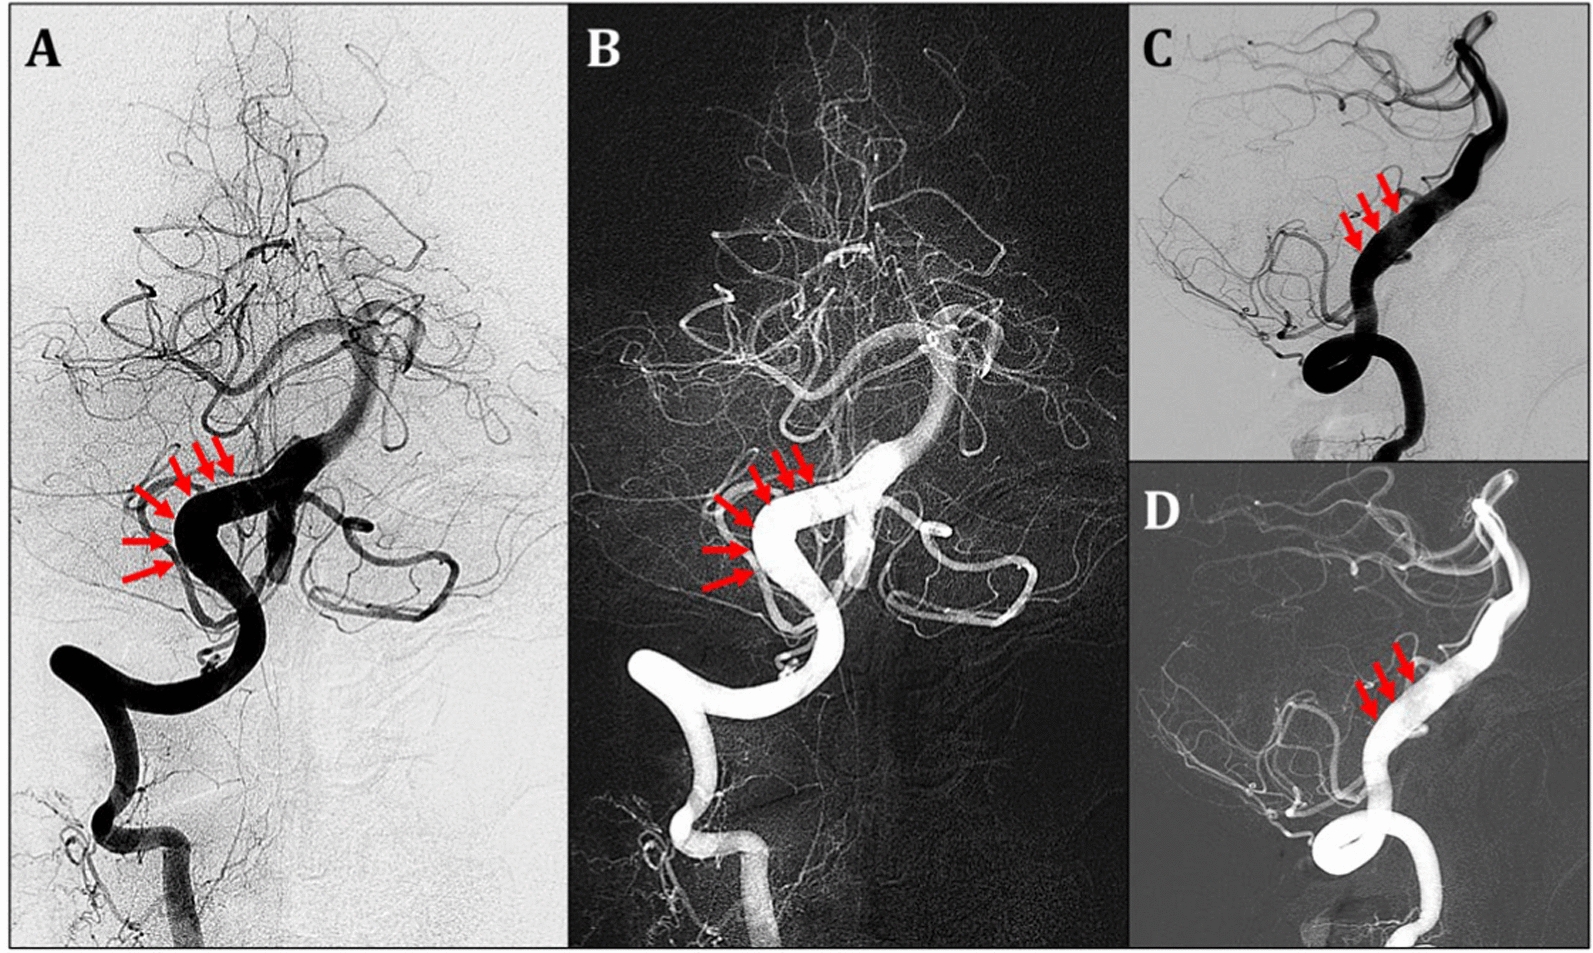

Recently, endovascular treatment (EVT) has emerged as a choice for VAD management due to its good efficacy, and low periprocedural morbidity. Endovascular procedures are performed when an ischemic stroke caused by VAD does not respond to AT medical treatment, there is stenosis or occlusion, or there is subarachnoid haemorrhage. Endovascular procedures such as stent angioplasty, double stent, stent-assisted coil and microvascular brain surgery (bypass) must be carried out promptly. According to a research study, the technique used to perform an EVT procedure for a VAD is determined by every fundamental condition of the case to be treated, as well as factors such as the patient's clinical symptoms, hemodynamic status, collateralization of the cerebral blood vessels, particularly the posterior circulation area, and significant features of the anatomy of blood vessels and perforators. If a VAD ruptures, the EVT procedure aims to close the ruptured area either by completely closing the VA or by performing stent-assist coiling. Meanwhile, for VADs that have not ruptured, the main aim of EVT is to ensure that the hemodynamic flow of cerebral blood is maintained using stenting. The choice of EVT treatment depends on the patency of the contralateral vertebral artery (VA) and the relationship between the dissection segment and the location of the origin of the posterior inferior cerebellar artery (PICA). Complete occlusion of the dissection segment is the best option. If the dissection is proximal or distal to the PICA without hypoplasia of the contralateral VA, treatment can be carried out with total occlusion of the dissection segment with a coil, where the PICA will obtain flow from the contralateral VA. If the VAD is present at the PICA branch, isolation of the dissected segment can be done by coil trapping with PICA revascularization via bypass surgery or PICA stenting [22, 23, 24]. The management therapy of EVT with stenting, and coil embolization or double stenting is shown in Figs. 4 and 5.

Fig. 4

A Case of Vertebral artery Dissection treated with EVT (Stenting + Coil embolization). A 60-year-old woman has severe nuchal on the right side and a history of hypertension ( +). From 3D-MRA and C-DSA Neuroimaging shown: A. 3D-MRA showed a dissecting aneurysm with fusiform dilatation at the right vertebra artery, segment V4; B. C-DSA showed a dissecting aneurysm with fusiform dilatation at the right vertebra artery from anterior–posterior (AP) view; C. C-DSA showed a dissecting aneurysm with fusiform dilatation at the right vertebra artery from lateral view; D. C-DSA showed a dissecting aneurysm with fusiform dilatation at the right vertebra artery from AP view of C-DSA Roadmap; E/F. Post-EVT procedures showed that a stent was inserted inside the lumen of the right VA with coil embolization. (The red arrow shows the dissecting aneurysm of the right vertebral artery.)